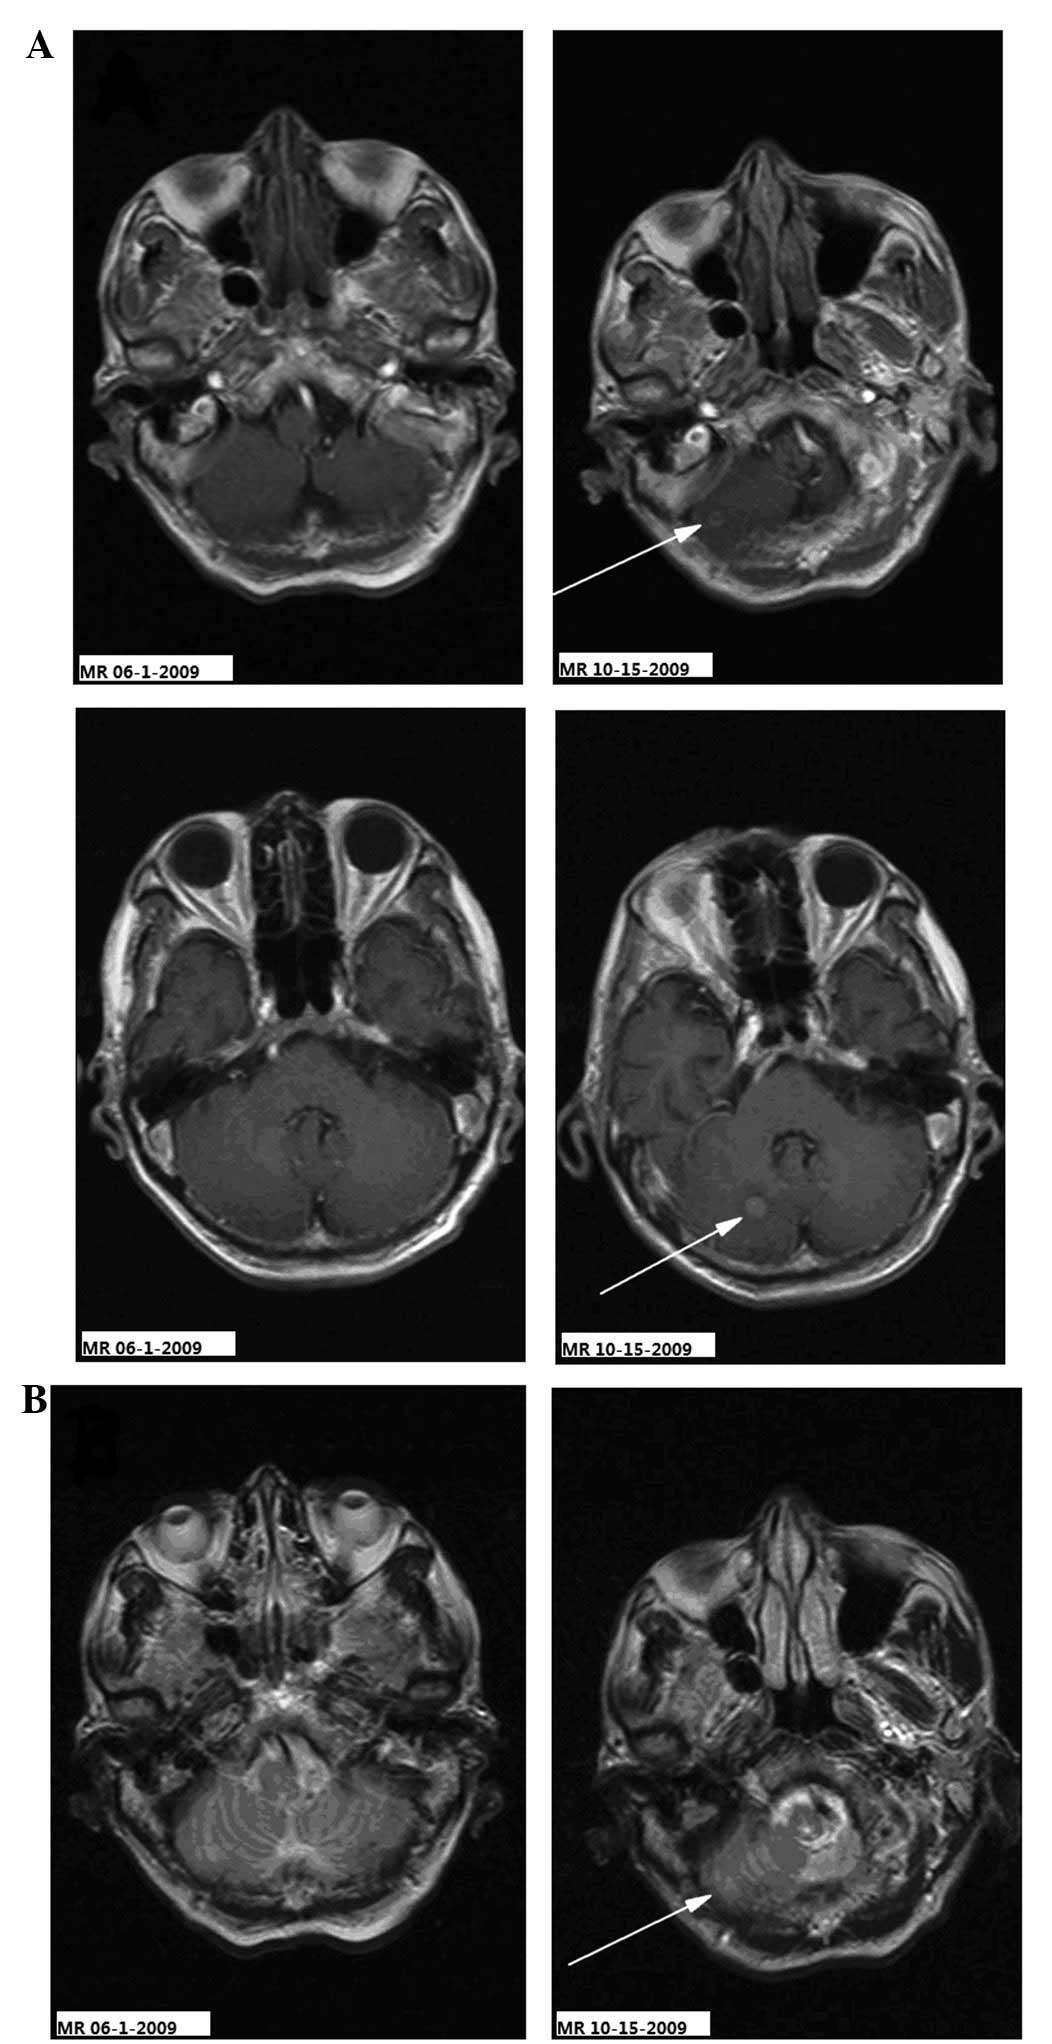

Comparison between the MR images of the cervical spinal cord prior to and following treatment. Sagittal T1-weighted images performed (A) prior to chemotherapy (MR 10-28-2009) showing abnormal signals in the medulla oblongata and cervical cord, considered to be the metastatic lesions (indicated by the two arrows), and (B) following chemotherapy (MR-11-23-2009) showing that the abnormal signals of the medulla oblongata and cervical cord had markedly improved (indicated by the two arrows). MR, magnetic resonance.

The patient complained of constant occipital headache with slight pain in the bilateral upper arm and fatigue, but no nausea or vomiting, for 2.7 months after the treatment of the primary lesion. The Karnofsky performance status (KPS) score was 70 and no pathological reflexes were observed on physical examination. Brain MRI revealed two nodules (0.35 and 0.8 cm in diameter) in the right cerebellar hemisphere. The signal was slightly lower in the unenhanced T1-weighted images and slightly higher in the T2-weighted images. The lesions showed clear ring-like, uniform hardening on signal-enhanced scans, and mild edema was observed surrounding the larger lesion. The diagnosis was of a cerebellar metastasis from the esophageal cancer following treatment (Figs. 3–5). Following whole brain radiotherapy of a total dose of 30 Gy/20 fractions of 1.5 Gy per fraction by hyperfractionation (two fractions per day), the patient’s occipital headache was relieved, however, the neck numbness was aggravated. A cervical MRI examination revealed enlargement of the medulla oblongata and spinal cord, with slightly increased T1 and T2 signals. A signal-enhanced scan showed heterogeneous enhancement in a region considered to be the metastasis. The patient continued with the planned whole brain radiotherapy, together with nedaplatin chemotherapy (40 mg on days one to three of the radiotherapy period). At the end of the first period of chemotherapy, the patient’s occipital headaches were alleviated and the neck numbness was markedly improved. One month later, the patient’s head and neck symptoms had further improved and a neck MRI revealed that the abnormal signal foci in the medulla oblongata and cervical cord had also markedly improved (Figs. 6 and 7). To strengthen the effects of the treatment, the patient was treated with palliative radiotherapy (total dose of 26 Gy/13 fractions of 2 Gy per fraction) to the cervical spinal cord. Following treatment, the patient’s head and neck pain and numbness symptoms had almost disappeared. The patient was discharged with oral etoposide (VP-16) capsules (50 mg daily for 20 days).

Figure 6

Comparison between the MR images of the cervical spinal cord prior to and following chemotherapy. Sagittal T2WI (A) prior to chemotherapy (MR 10-28-2009) showing increased T2WI signals and abnormal morphological augmentation in the medulla oblongata and cervical cord indicating metastatic lesions (indicated by the two arrows), and (B) following chemotherapy (MR 11-23-2009) showing decreased T2WI signals in the medulla oblongata and cervical cord consistent with the signals of normal tissues, and marked improvement in the abnormal morphology (as indicated by the two arrows). MR, magnetic resonance; T2WI, T2-weighted image.